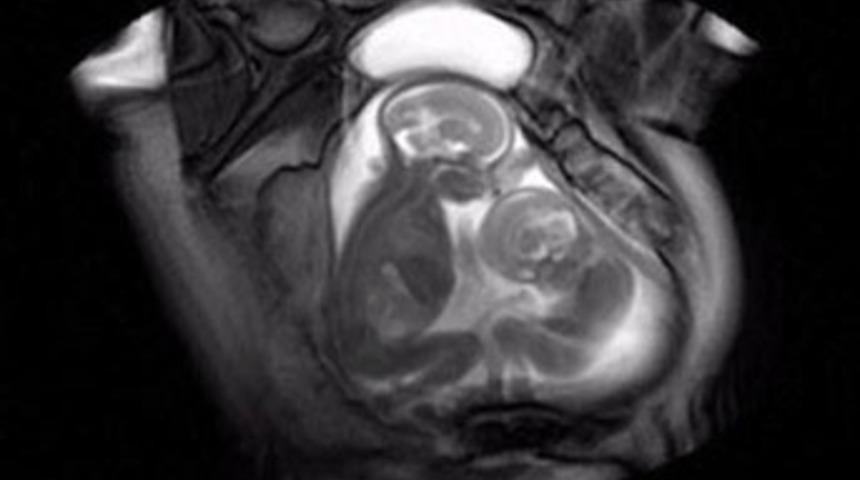

İngiltere’de bir üniversitenin bebek sağlığı merkezinde annelerinin karnında görüntülenen ikiz bebeklerin “yer kavgası” doktorları şaşırttı.

İngiltere’nin Londra kentinde bulunan Imperial College’da MR’a giren hamile kadının karnındaki ikiz bebekler kendilerine daha çok yer açabilmek için dar alanda birbirilerini tekmelerken görüntülendi.

Üniversite’de yapılan çalışma “İkizden kardeşine nakil sendromu” olarak adlandırılan ve tek yumurta ikizlerinin arasında kan dolaşımına neden olarak birinin diğerinden daha az gelişmesiyle sonuçlanan durumu gözlemlemek için gerçekleştirilmişti.